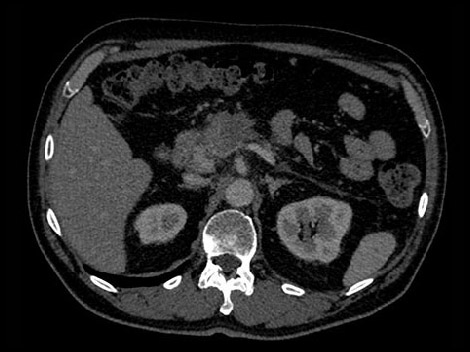

W celu zobrazowania możliwości tomografu komputerowego z detektorem spektralnym prezentujemy dwóch hipotetycznych pacjentów o takim samym profilu zdrowotnym, narzekających na ból brzucha. Ich lekarze zlecili badanie metodą tomografii komputerowej, aby uzyskać więcej danych. Jeden z pacjentów został poddany badaniu metodą konwencjonalnej tomografii komputerowej, a drugi — tomografii komputerowej z użyciem detektora spektralnego. W przypadku obu pacjentów przebieg procedury jest taki sam. Niemal identyczny jest również sposób pracy personelu szpitala.

Wiek: 51 Wzrost: 183 cm" Masa ciała: 79 kg Skan CTA jamy brzusznej z 70-sekundowym opóźnieniem wstrzyknięcia środka kontrastowego

W celu ustalenia jednoznacznego rozpoznania w tym hipotetycznym przypadku radiolodzy potrzebują większej ilości informacji na temat guza widocznego w trzustce.

Jeśli obraz uzyskany tradycyjną techniką tomografii komputerowej nie daje jednoznacznych odpowiedzi, konieczne może być poddanie pacjenta dodatkowemu obrazowaniu.